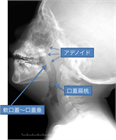

1. 扁桃肥大(アデノイド肥大を含む)は小児の睡眠時無呼吸(obstructive sleep apnea:OSA)を含む閉塞性睡眠時呼吸障害(obstructive sleep-disordered breathing:oSDB)の最も一般的な原因であり、このような小児患者に口蓋扁桃摘出術 ± アデノイド切除術は非常に有効である。一方、扁桃肥大は成長とともに軽減すること、術後出血などの術後合併症もみられることから、手術適応は慎重に評価しなければならない。成人の扁桃肥大では腫瘍性病変の可能性を念頭に置いて診断を進める必要がある。